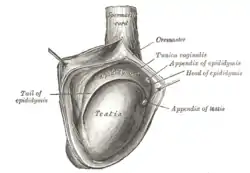

The right testis, exposed by laying open the tunica vaginalis. (Tunica vaginalis is labeled at upper right.) | |